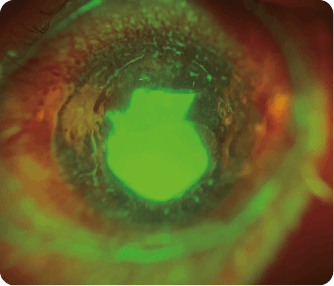

Multimedya – Foto Galeri Foto Galeri Úlcera Corneal Quiste Corneal Pterigion Descemetopexia Implante ICL Keratitis Marginal Migración de aceite de silicona Patrón de flor de Iris Foto Galeri